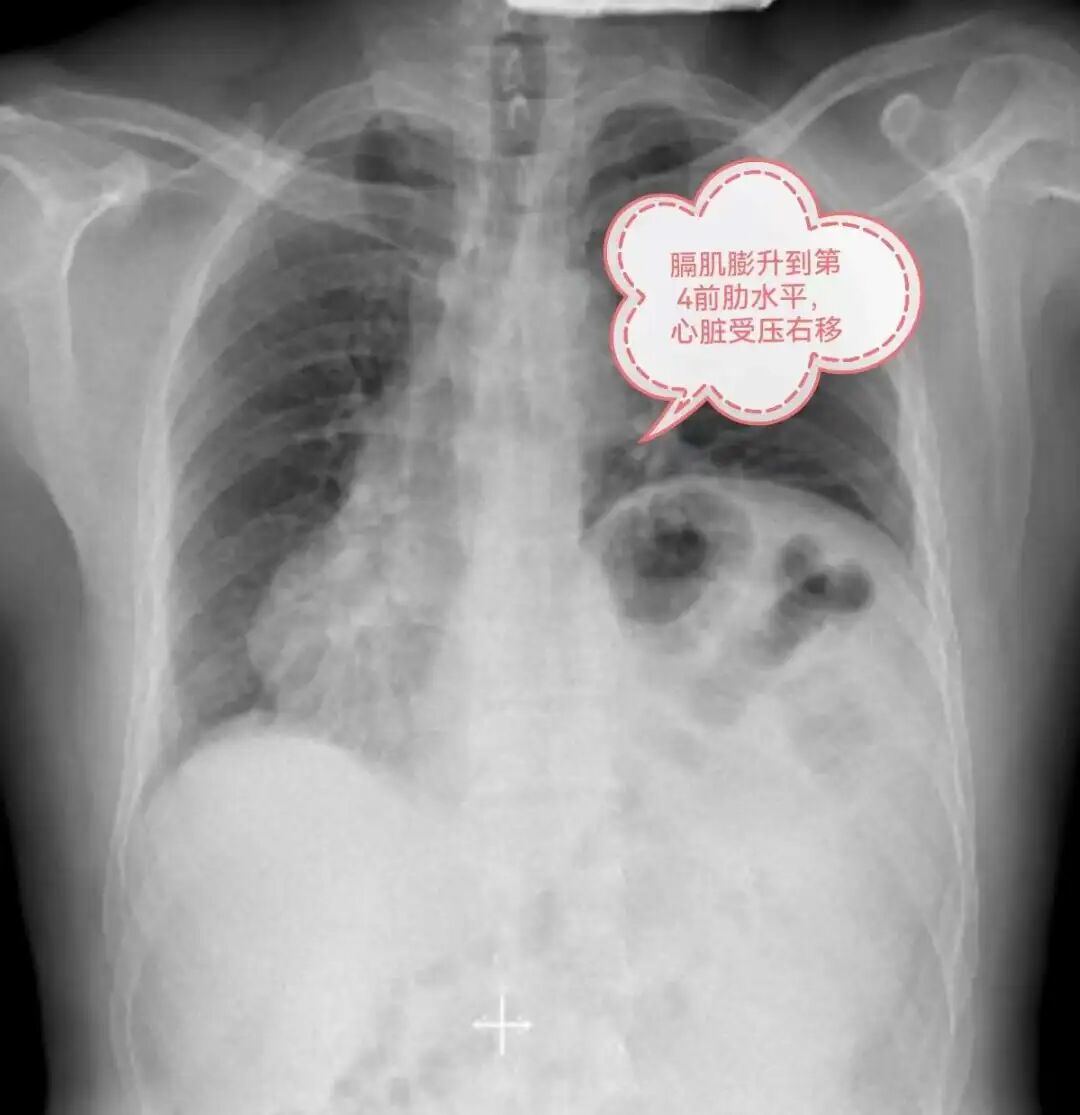

近日,家住遵义的一名55岁患者李某,因活动后喘累、气促多年,辗转多家医院就诊无果,终于在贵州航天医院成功治疗。 病情回顾 几年前,李先生爬坡上楼就开始有点喘累、呼吸急促,但是自己并未引起重视。 第一次入院贵阳某三甲医院 1年前,李先生症状加重,爬到2楼中途都需要缓口气休息,于是到当地某大型三甲医院就诊,入住心血管内科,做了心脏血管造影、心脏彩超、胸部CT、抽血化验等很多检查,住院两周,医生告诉他心脏没什么大问题,仅是左侧胸腹腔之间的膈肌位置有点抬高,心脏位置有些右偏,属于先天异常,无需治疗,随即李先生办理出院。 第二、三次辗转贵阳某三甲医院 李先生的症状仍没有得到缓解,又先后辗转到贵阳市2家三甲医院就诊,同样诊断为膈膨升症,两家医院均未给出缓解症状和治疗的合理方案,于是李先生又开始继续寻医之路。 西南医院医生推荐 贵州航天医院 热心邻居向他推荐去西南医院,在咨询该院医生后,医生建议李先生“不用跑这么远,到贵州航天医院一样可以治疗”。 李先生来到贵州航天医院门诊,刚好遇上心胸外科陈光春主任坐诊专家门诊,陈主任听闻李先生的病情后,详细介绍了膈膨升症的相关问题,并告诉他手术后的效果,为他仔细分析病情,告诉他“心脏虽然位置有些右偏,但心功能是正常的,不会影响手术效果”。 入院后第4天,心胸外科团队经过充分的术前准备,在全麻下为李先生行电视胸腔镜微创膈肌折叠缝合术,术后各项指征恢复正常,顺利出院。出院后,爬坡上楼再也不累了、不喘了,一口气走上4楼也没问题。 为此,李先生感叹历时1年多,走了这么多家大医院,最终选择在贵州航天医院就诊,无论是门诊、手术室,还是住院部、辅助检查科室,医护人员服务态度都非常好,解释病情也非常耐心仔细,让人感觉非常专业非常有水平,所以才决定就在贵州航天医院手术治疗,治疗效果也证实自己的选择是非常正确的。 在医院的晨读会上心胸外科就介绍过“膈膨升症”疾病的知识,以及采取的微创手术治疗效果。此次李先生首次挂号的并非心胸外科,而是挂的呼吸科,因呼吸科的门诊医生听患者自我阐述在其他医院诊断是膈膨升症,呼吸科医生立即带患者到心胸外科门诊就诊。 贵州航天医院每周三举行的“晨读会”,通过不同学科、不同专业的讲解汇报,拓展医院各层级医务人员的知识结构,解决临床遇到的难点和问题,凝聚发展合力,以医院晨读会推动各科室形成常态化学习机制,营造全院比学赶超良好氛围,进一步提升医疗服务质量,以“小进步”促进“大发展”,为健康遵义建设贡献医院力量。 科 普 什么是膈膨升症? 膈膨升症被称为膈肌膨出症,属膈肌无力类疾病,膈肌活动强度减弱,包括膈肌麻痹和膈肌膨出症。 狭义的膈膨升症是指:由于胚胎横中隔内肌肉组织发育异常,导致膈肌先天性缺陷引起的膈肌膨出,称为先天性(或原发性)膈膨升症。 广义的概念通常被用来指膈肌纤维因发育不良、萎缩而异常的抬高,包括膈神经的不明病因、不明部位的损伤造成的膈肌抬高,称为获得性(或继发性)膈膨升症。 膈膨升症应该如何治疗? 膈膨升症只有在产生症状时才具有临床治疗意义,原因如下: (1)药物不能控制的呼吸功能衰竭; (2)伴胃肠道梗阻症状时; (3)不能与肿块膈疝鉴别的病例。 1947年Bisgand首次对膈膨升症进行了手术治疗并获得成功,其关键是通过手术阻止膈肌继续上移和消除矛盾运动。手术方法是膈肌折叠术,包括膈肌不切开折叠法膈肌切开折叠法和膈肌部分切除后的对端褥式缝合法。 近年来多采用电视胸腔镜微创膈肌折叠术,其膈肌折叠法因为能在电视屏幕直视下缝合避免损伤膈下脏器而更加安全可靠。电视胸腔镜手术治疗效果满意,创伤较传统开胸手术轻微,手术并发症及死亡率很低。术后患者动脉血氧分压和氧饱和度显著提高,通气功能明显改善,活动后气促等症状明显改善甚至消失。 贵州航天医院心胸外科简介 心胸外科是诊治疾病种类较为复杂,专科性非常强的一门学科。心胸外科手术难度大,风险高,对设备和配套要求也高,大众对心胸外科经常会存有误解,误认为心胸外科只是看胸外面的病,这就很容易让人联想到乳腺疾病等,其实胸外科主要看的是胸腔内的病,主要是食管、气管及肺上的疾病。如食管囊肿、食管平滑肌瘤、贲门失迟缓症、严重的反流性食管炎、食管裂孔疝、自发性食管破裂、食管、气管瘘、食管癌、食管胃交界处癌(贲门癌)、肺大疱(有时破裂引起自发性气胸)、肺脓肿、肺隔离症、肺结核球、肺结节等需到心胸外科就诊。 心胸外科导航 贵州航天医院呼吸综合楼003诊室 住院病区:呼吸综合楼4楼 门诊坐诊时间 每周一至周五 (08:00—12:00; 14:00—17:00) 咨询电话 住院病区咨询电话:27677360(医生办公室);0851-27677732(护士站) 心胸外科专家